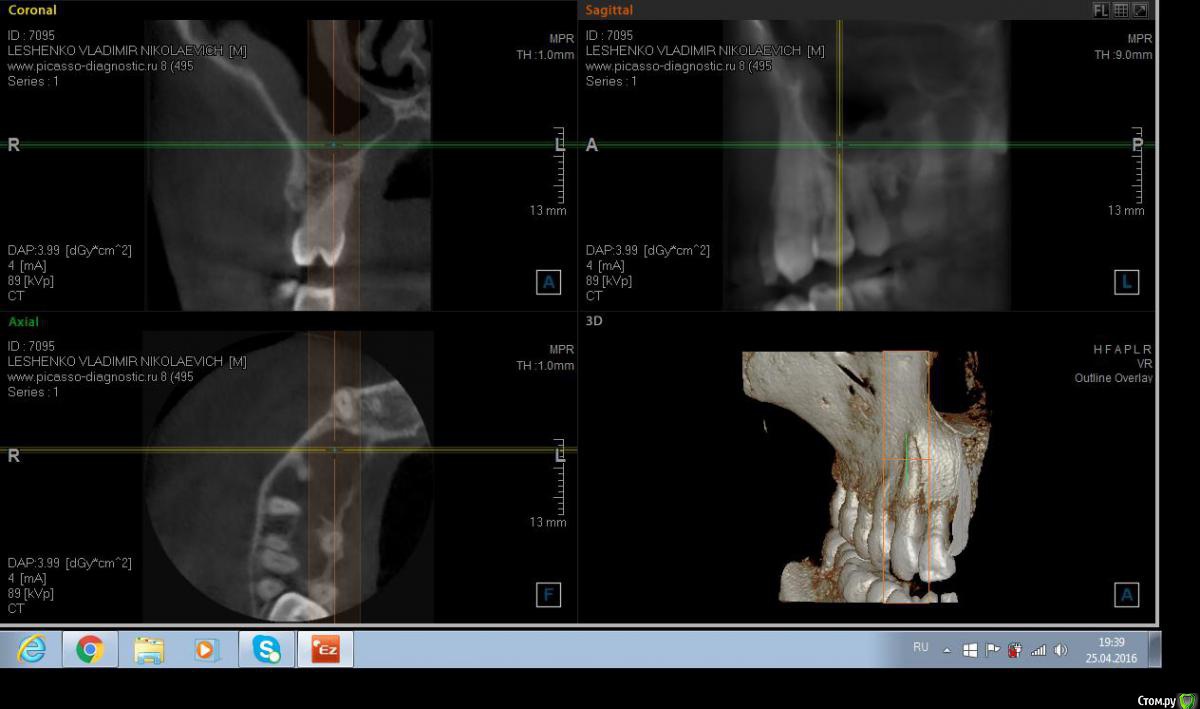

Salma Опубликовано 26 апреля, 2016 Поделиться Опубликовано 26 апреля, 2016 Обратился пациент с болью в области десны в районе 15 и 16 зубов, при осмотре немного отечная десна в области этих зубов, на небе ( не знаю как сказать по другому) между этими же зубами есть щель, с небольшим количеством отделяемого. В общем то промыла , положила метрогил, отправила на кт. Похоже на корень , думаю удалять, но вопросы такие: 1. достаточно ли просто удалить или нужно будет костью присыпать? и что там насчет гайморовой? Ссылка на комментарий

red_butler Опубликовано 26 апреля, 2016 Поделиться Опубликовано 26 апреля, 2016 Да похоже на корень от первого моляра. Просто удалить. Ссылка на комментарий

wladdX Опубликовано 26 апреля, 2016 Поделиться Опубликовано 26 апреля, 2016 Похоже нёбный корень от шестого. Удаляйте. 1 1 Ссылка на комментарий

Salma Опубликовано 26 апреля, 2016 Автор Поделиться Опубликовано 26 апреля, 2016 спасибо ответившим, я думаю что скорее молочный, так как шестерка у пациента есть Ссылка на комментарий

red_butler Опубликовано 26 апреля, 2016 Поделиться Опубликовано 26 апреля, 2016 спасибо ответившим, я думаю что скорее молочный, так как шестерка у пациента естьа восьмой есть? Судя по наклону и расстоянию до премоляра, похоже что все таки от шестерки. Ссылка на комментарий